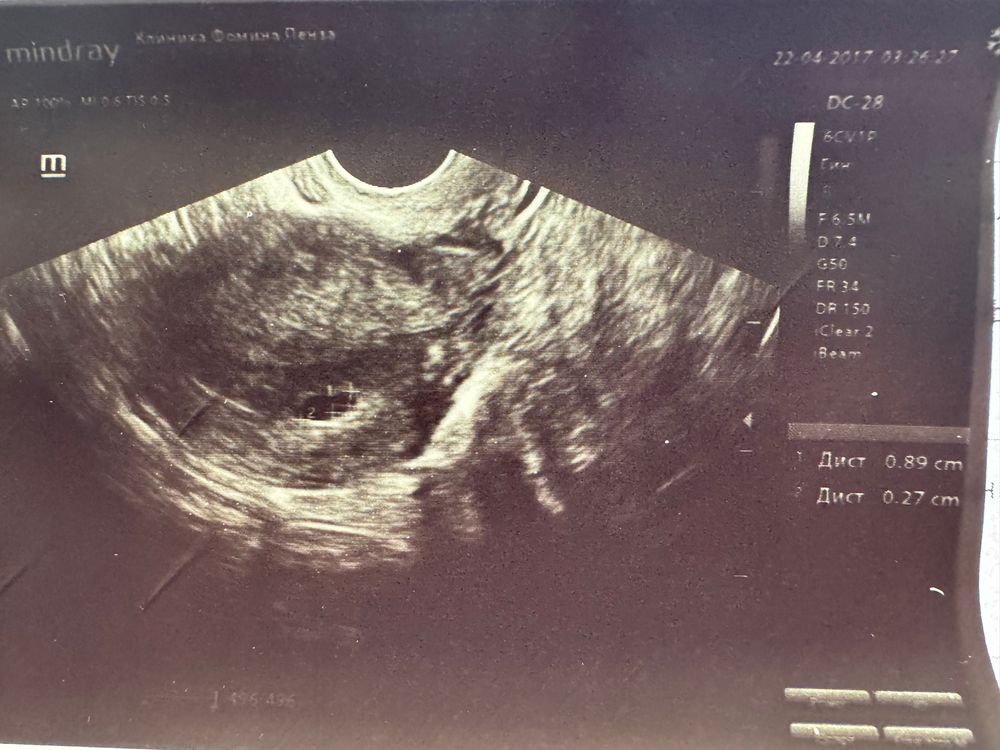

18 ДПП Наше первое УЗИ 🥳

Ксения, эмбриончик пока не увидели, там желточный мешочек 🤭 Малышок пока совсем козявка, не разглядеть)

Первое узи на 22 дпп УЗИ и хгч